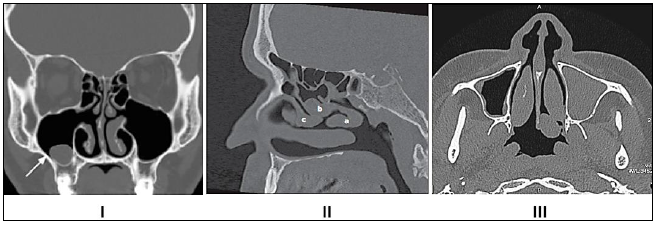

Com base na imagem radiológica apresentada, os números expostos referem-se, respectivamente, a quais estruturas anatômicas?